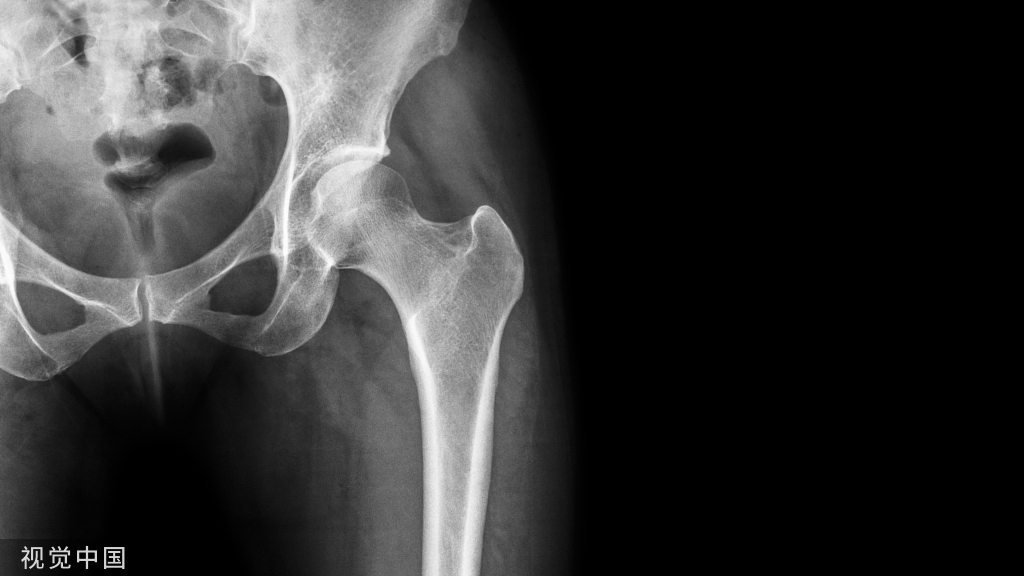

事件的易感性增加。全膝关节置换术(totalknearthroplasty,TKA)常用于治疗老年人重度膝关节疾病,作为一个强烈的应激源,可能导致老年衰弱患者身体不成比例的功能损害,术后出现各种不良事件。术前衰弱评估有助于筛查术后预后不良的高危患者,降低TKA术后并发症及死亡的发生率,让患者更快更好地得到治疗和康复。但是,目前有关术前衰弱评估与TKA术后加速康复的关系却鲜有文献进行分析。本文就术前衰弱评估与TKA术后加速康复的关系进行了探讨。

衰弱是一种与增龄相关的老年综合征,可增加老年人跌倒、失能和死亡等风险[1-2]。衰弱的特征是生理储备功能减弱、多系统功能衰退、机体保持内环境稳定的能力下降、对应激事件的易感性增加[3-4]。衰弱并不总与疾病状态相关,而是涉及神经肌肉和代谢免疫等多个生理系统储备能力的下降[5-6]。全膝关节置换术常用于治疗老年人重度膝关节疾病,作为一个强烈的应激源,可能导致老年衰弱患者身体不成比例的功能损害,术后出现各种不良事件[7]。